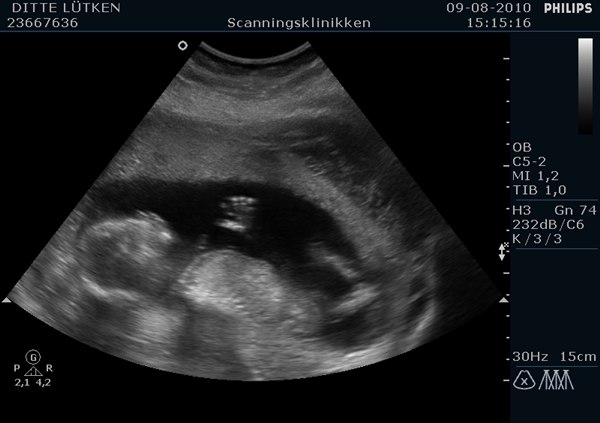

I får lige billeder af først tappen, man ser det nedefra mellem benene, og et andet billede hvor Bimmeren lige vinkede engang!